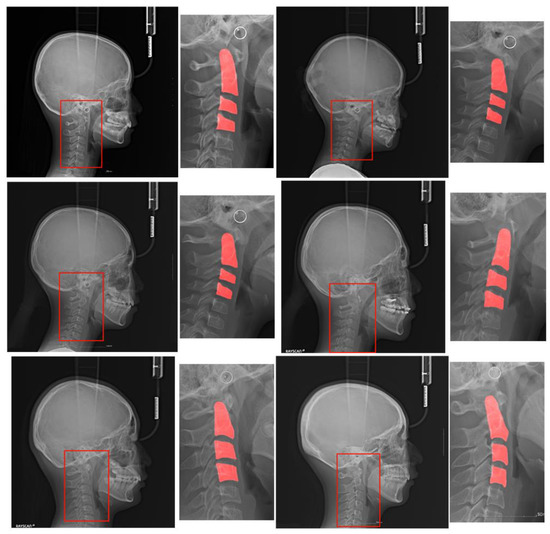

- The C2, C3, and C4 cervical vertebrae are very small compared to the whole image, resulting in a severe data imbalance. To solve this issue, we propose attention U-Net models that automatically detect the ROI and segment the C2, C3, and C4 regions with high accuracy.

- We propose three CNN-based classification models: a one-step model with only CVM classification, a two-step model with ROI detection and CVM classification, and a three-step model with ROI detection, cervical segmentation, and CVM classification. Their accuracies were compared with those of our dataset.